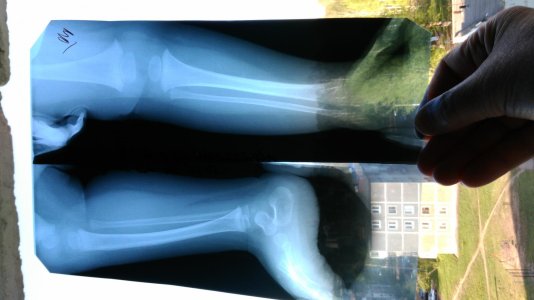

Здравствуйте! Ребёнок,1 год 2 месяца, разогнался и неудачно присел, не мог после этого наступать на правую ногу. На снимке хирург увидел трещину в голеностопе, наложили лангетку,сказали не давать опираться на ногу пока носим её,наложили на 10 дней. Когда разрешается опираться на ногу,подскажите пожалуйста.хирург наш ничего не сказал,сейчас ушёл в отпуск,другого хирурга в городе нет...

Наши снимки

Вложения

• IMG_20160506_080422.jpg

IMG_20160506_080422.jpg

172,4 КБ · Просмотры: 440

• IMG_20160506_080541.jpg

IMG_20160506_080541.jpg

165,3 КБ · Просмотры: 414